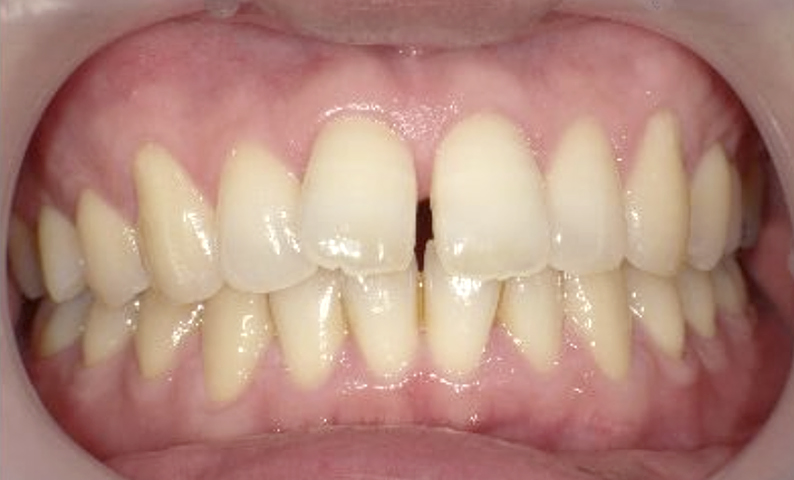

症例_002 上顎だけの部分矯正

治療期間:7ヶ月金額:30万円+税女性前歯のガタガタ上の前歯だけ

| Before | After |

|---|---|

|